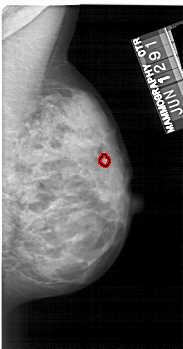

A_1220_1.LEFT_MLO

LEFT_MLO LINES 5491 PIXELS_PER_LINE 2866 BITS_PER_PIXEL 12 RESOLUTION 43.5 NON_OVERLAY

FILE: A_1220_1.RIGHT_MLO.OVERLAY

TOTAL_ABNORMALITIES 1

ABNORMALITY 1

LESION_TYPE CALCIFICATION TYPE PLEOMORPHIC DISTRIBUTION CLUSTERED

ASSESSMENT 4

SUBTLETY 3

PATHOLOGY MALIGNANT

TOTAL_OUTLINES 1

BOUNDARY